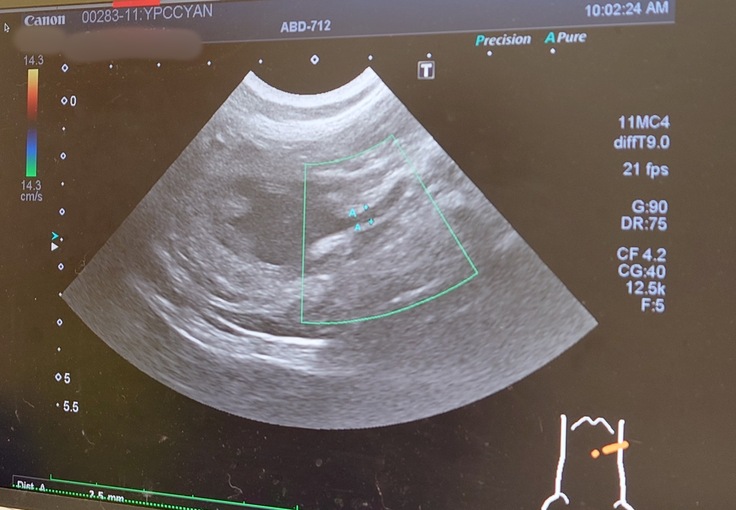

🐈「なるほど。今日はエコー検査と血液検査と尿検査と触診ですか。さぁ、やりましょうか。」

🐈変わらず、腎臓と腎盂は肥大したままのヨッちゃん🐈

🐈尿管も拡張したままだった。前回と変わりなく現状維持といったところ。🐈

今回も通院を頑張ってくれたヨッちゃん。定期的な尿路感染を起こしていないかの検査とサプリと薬の処方はかかりつけの動物病院でやってもらって、尿路感染を起こした場合やその可能性がある場合、腎臓腎盂の肥大や尿管拡張に変化が診られた場合は市外の専門の動物病院で詳しく診てもらうという予定になりました。消化器サポート系の療養食と尿の健康を維持するサプリとうんちを柔らかくするお薬を飲みながら、尿路感染を起こさないように、現状維持を保てるようにヨッちゃんにも頑張ってもらいながら1日1日を過ごしていきたいと思います😊